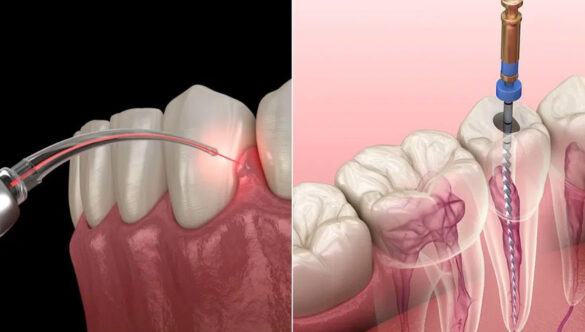

At NOVA Dental Hospital, Dr. Happy Patel has curated a state-of-the-art facility that is designed to provide a calming and premium atmosphere for patients. Located conveniently in the heart of Gandhinagar, near Gift City and PDPU, the clinic is equipped with cutting-edge technology and world-class amenities. The clinic boasts advanced equipment such as nitrous oxide inhalation sedation, which ensures a painless and anxiety-free experience for patients; a dental laser for precise, minimally invasive treatments; and a high-end in-house scanner that allows for accurate digital impressions. The unique operating theater-style dental chair setup for surgical procedures further highlights the clinic’s commitment to patient comfort and safety.

Dr. Patel’s philosophy centersaround providing a patient-first experience, where the highest standards of care are delivered with compassion and precision. She uses advanced tools such as the NSK endomotor, J. Morita apex locator, high-class Vatech X-ray setup, and an in-house dental scanner for accurate diagnosis and treatment. The clinic also specializes in a wide range of dental services, including root canal therapy, wisdom tooth removal, composite fillings, zirconia crowns, E-Max veneers, and much more. For those needing full-mouth rehabilitation, dental implants, or flap surgery, NOVA Dental Hospital offers a comprehensive suite of services with remarkable attention to detail.